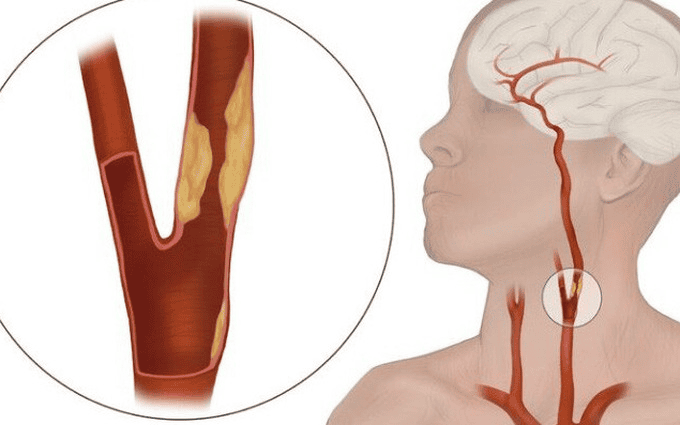

TS.BS Trần Chí Cường trả lời: Thuốc lá tàn phá hệ tim mạch một cách khủng khiếp. Khi khói thuốc lá xâm nhập vào phổi, nó sẽ qua các màng trao đổi khí ở phế nang và cạnh tranh với hồng cầu sinh ra yếu tố viêm. Yếu tố viêm ở góc tự do sẽ làm tổn thương thành mạch máu, nó khiến mạch máu người hút thuốc bị xơ cứng đi và giảm khả năng chuyển oxy của hồng cầu.

Nếu hút thuốc lá nhiều, các mao mạch sẽ bị tổn thương. Dần dần, nó lan ra và bắt đầu hình thành cục máu đông gây tổn thương thành mạch, khiến mạch máu bị xơ cứng. Hậu quả cuối cùng là gây tắc nghẽn mạch máu.

Bất kỳ mạch máu nào trên cơ thể người nghiện thuốc lá cũng đều có thể bị tổn thương. Nếu mạch máu não bị tổn thương sẽ gây ra đột quỵ não. Nếu mạch máu ở cơ tim bị tổn thương sẽ dẫn đến tình trạng nhồi máu cơ tim cấp. Tắc nghẽn mạch máu ở chi sẽ gây hoại tử chi. Nếu mạch máu thận bị tắc nghẽn, người bệnh sẽ bị suy thận mãn.